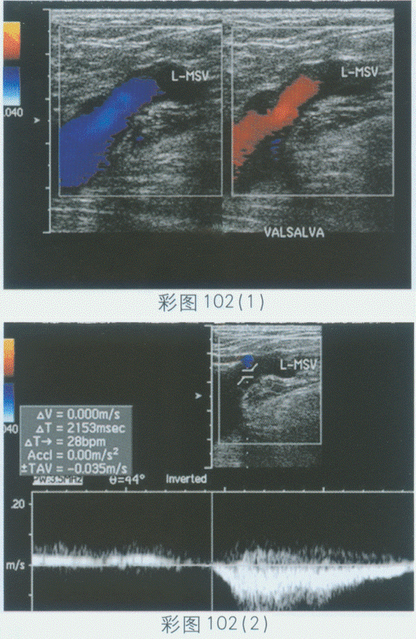

临床资料:男,40岁,自述活动后感左下肢沉重乏力。临床物理检查:左下肢内侧可见蚯蚓状纡曲隆起,皮肤无溃烂。超声综合描述:左大隐静脉增宽,左下肢深静脉管壁光滑连续,管腔内未见异常回声,探头加压后管腔消失,CDFI:左下肢深静脉及大隐静脉内血流通畅,Valsalva试验:大隐静脉内可见血流色彩逆转,PW:左下肢深静脉血流频谱形态正常,大隐静脉出现反向频谱,持续时间2.1秒。见彩图102。

超声提示()。

A.左大隐静脉正常声像图

B.左股浅静脉瓣膜功能不全

C.左大隐静脉曲张左隐一股静脉瓣膜功能不全

D.左股总静脉瓣膜功能不全